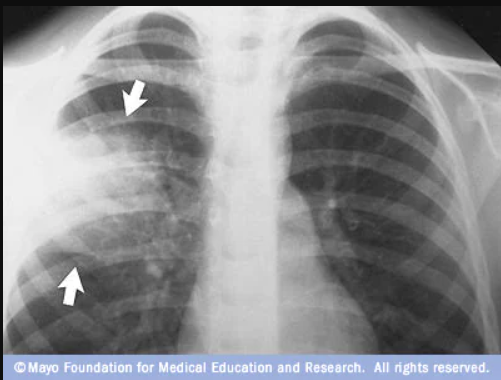

Diagnostico Clínico - radiológico

- El diagnóstico de neumonía es clínico-radiográfico: la historia clínica y examen físico sugieren la presencia de una infección pulmonar, pero el diagnóstico se confirma cuando se demuestra la presencia de infiltrados pulmonares en la radiografía de tórax y se descartan los diagnósticos diferenciales. La historia clínica, el examen físico y los hallazgos de la radiografía de tórax no permiten predecir el agente causal de la infección pulmonar; los síntomas, signos clínicos y hallazgos radiográficos se superponen entre los distintos agentes causales (bacterias clásicas y atípicas, virus respiratorios). En el siguiente cuadro se resumen los aspectos claves para reconocer una neumonía

- El diagnóstico clínico de neumonía sin confirmación radiográfica carece de precisión ya que el cuadro clínico (anamnesis y examen físico) no permite diferenciar con certeza al paciente con neumonía de otras condiciones respiratorias agudas (infecciones de la vía aérea superior, bronquitis, bronquiolitis, influenza, exacerbaciones de asma o EPOC, bronquiectasias, tuberculosis pulmonar) u otros diagnósticos diferenciales (insuficiencia cardiaca congestiva, tromboembolismo pulmonar, neoplasia pulmonar)